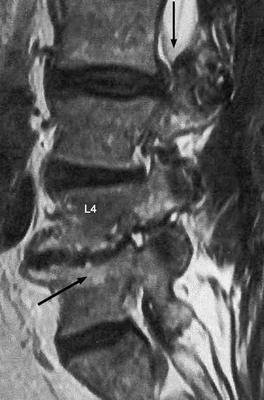

Does your back look like this, but with the BMP?

I had a lumbar synovial cyst L4-5, with subsequent decompression only. 4-6 weeks later, the pain came back.

Repeat imaging showed resection of the initial cyst, but a new one had formed. Then had a fusion at L4-5 with BMP. It was great for 6 months.